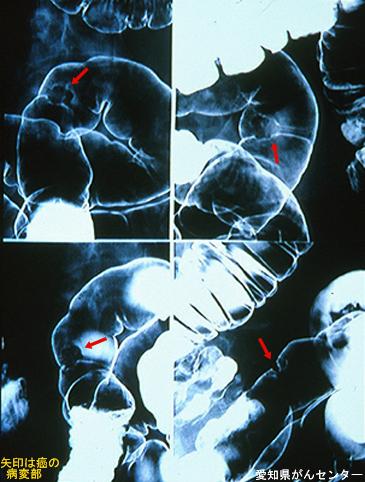

疾病(病理主体)的分类恶性上皮性肿瘤/腺癌

部位(按器官分)大肠/乙状结肠

检查方法X线

肿瘤的肉眼分类0型(表在型)/IIa型(IIa+IIc)

肿瘤最大直径15~19

肿瘤的深度sm